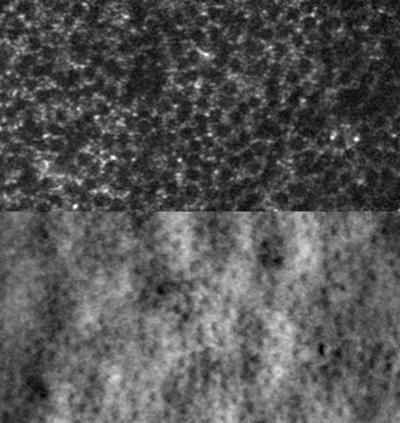

Sub-diffraction limit image of foveal cone photoreceptors

Sub-diffraction limit image of foveal cone photoreceptors imaged using 1060 nm adaptive optics optical coherence tomography (AOOCT). (Top) En face view of the AOOCT. (Bottom) Single cross-sectional slice (B-scan) through the horizontal line. Read the associated publication.